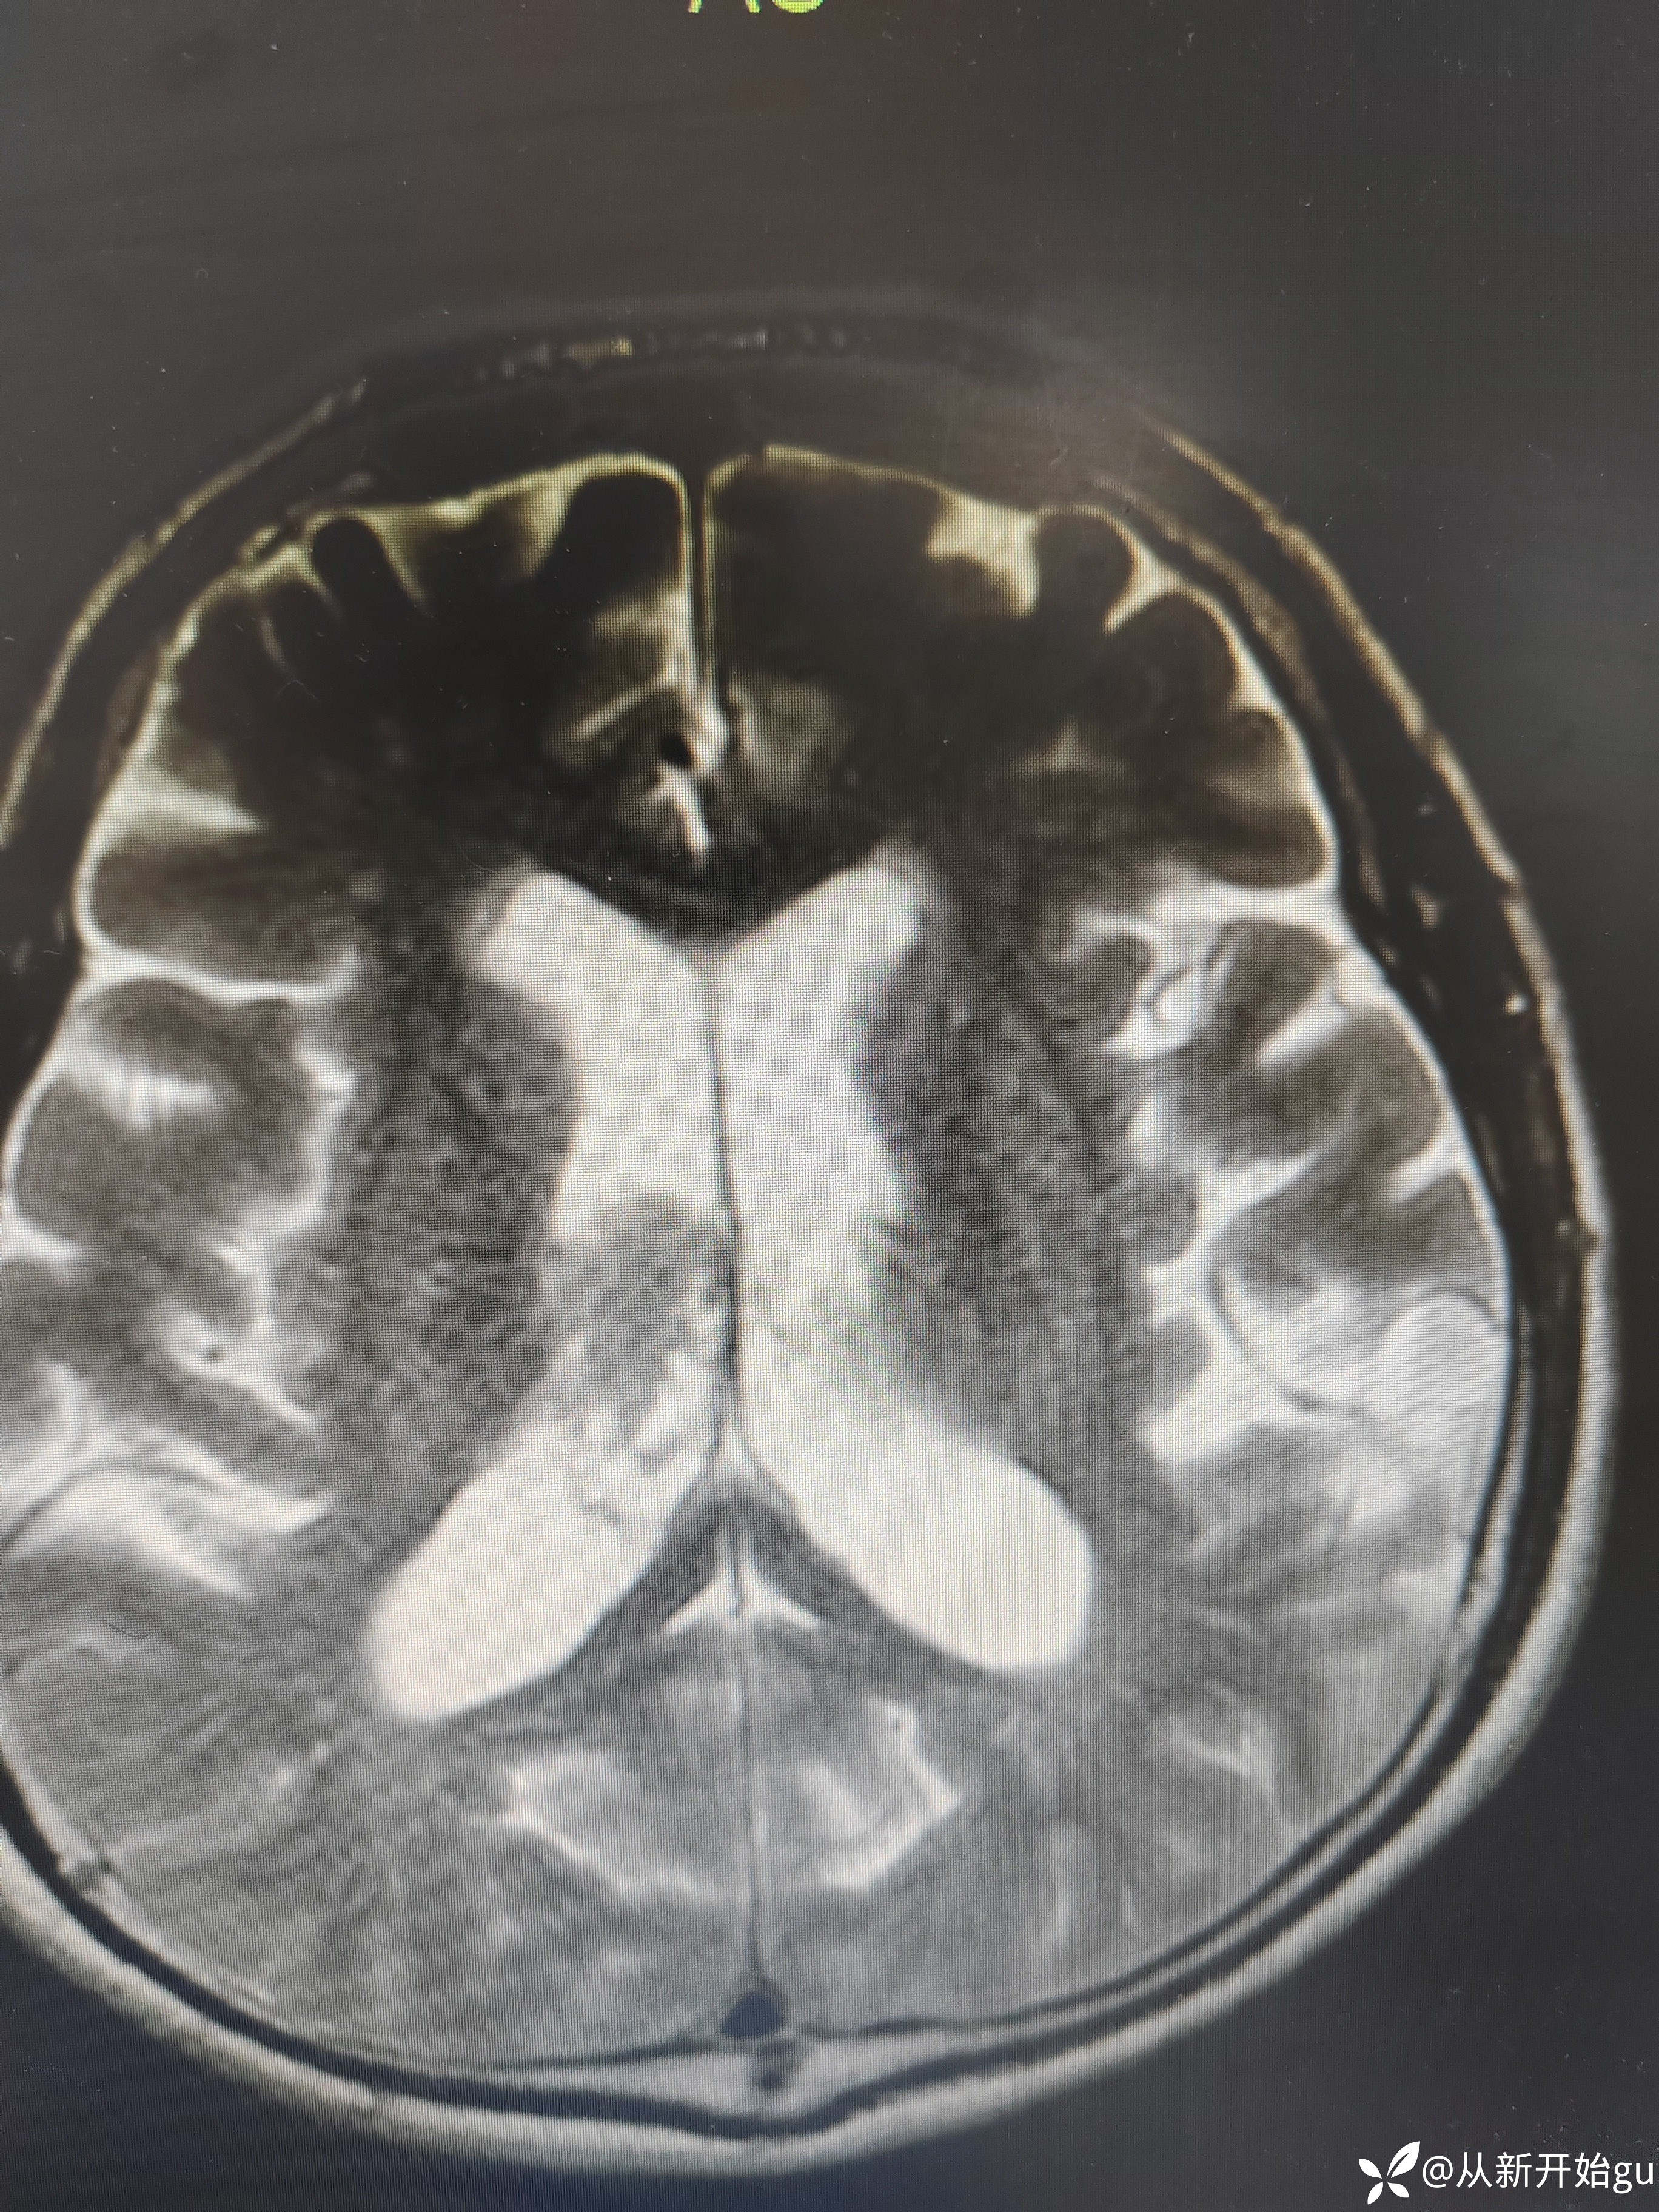

完善核磁:T2

完善核磁:T2